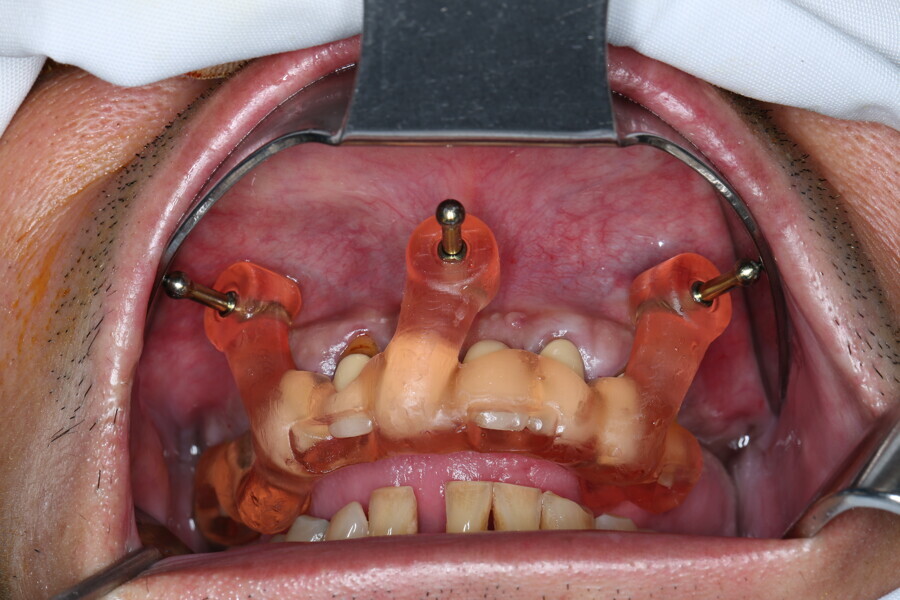

Compromised maxillary dentition treated with Straumann Pro Arch and a digital workflow